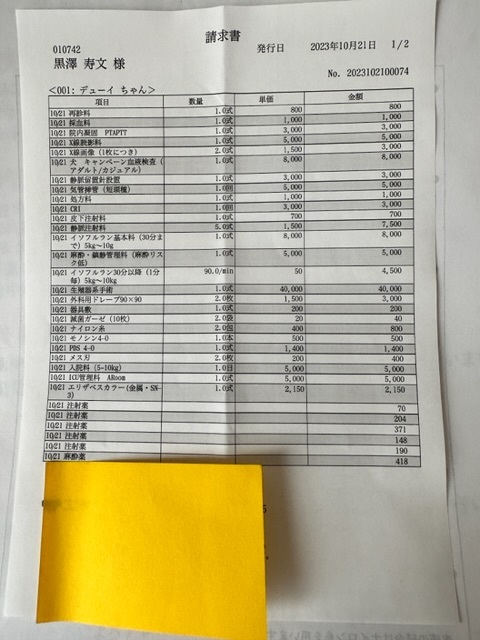

★陰唇低形成手術 (11月に手術予定)

更に詳しい検査によりおしっこをする陰部が凹みその上を脂肪が覆いかぶさっている状態でじゃーっと出す際、凹んだ部分が邪魔して脚に伝わって垂れる状態となっています。

会陰形成術を11月に予定しております。

クラウドファンディング目標金額690.000円

会陰形成手術にかかる見積もり金額

130.824円

※上記は大学病院で頂いた診断書

※下記は初診かつ、会陰形成術をして頂く動物病院より発行して頂いた診断書、治療計画書

下記は次回会陰形成手術による請求、見積もり金額となります。

会陰形成術 130.824円